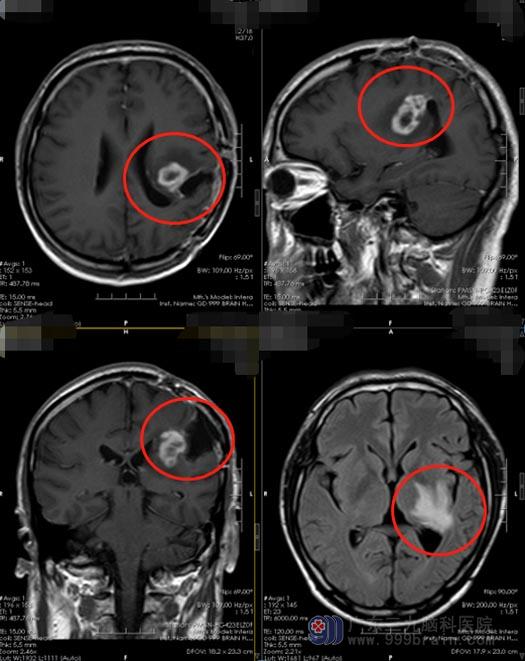

2020年开始,刘先生出现反复的右侧肢体麻木,家里人有点担心了,他们决定到广东三九脑科医院仔细看看。进一步头颅MR检查结果提示:“左侧顶部呈术后改变,左侧顶叶局部软化灶形成并胶质增生,增强后其内斑点状轻度强化,邻近左侧顶叶缘上回区域结节状异常强化,不除外肿瘤性病变”。刘先生的心顿时凉了半截,肿瘤复发了。